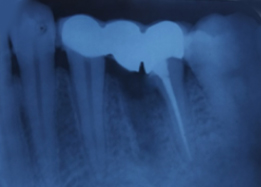

Hemisectomy

Immediate Post-Surgical IOPAR

Pre-OP IOPAR